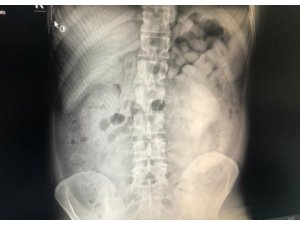

Doktor muayenesi ve çekilen film sonucunda şüphelinin sindirim sisteminde 800 gram eroin maddesi ele tespit edildi.